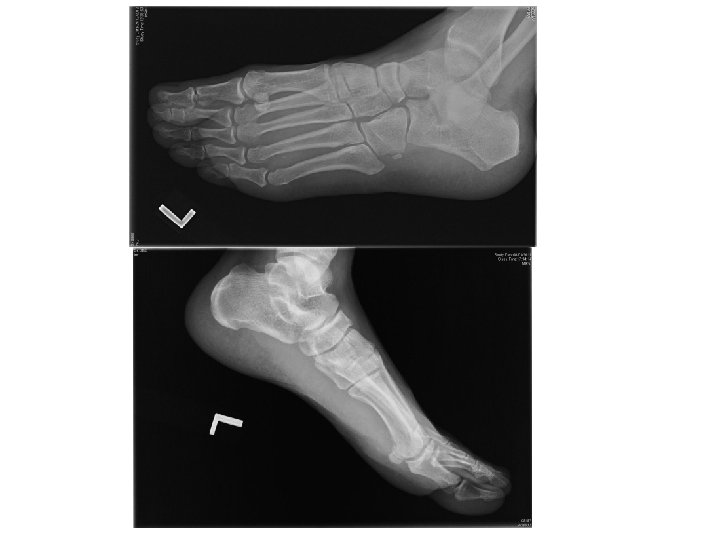

Case 1 • • M/52 Walk unaided to AED c/o left foot sprain few

Case 1 • • M/52 Walk unaided to AED c/o left foot sprain few days ago during working P/E swelling, tender over dorsum of foot

Questions • What were the X ray findings • What was the name of

Questions • What were the X ray findings • What was the name of the sign showed in Xray? • What was this injury call? • What was the classification of this injury • What was the optimal management • What were the important complications